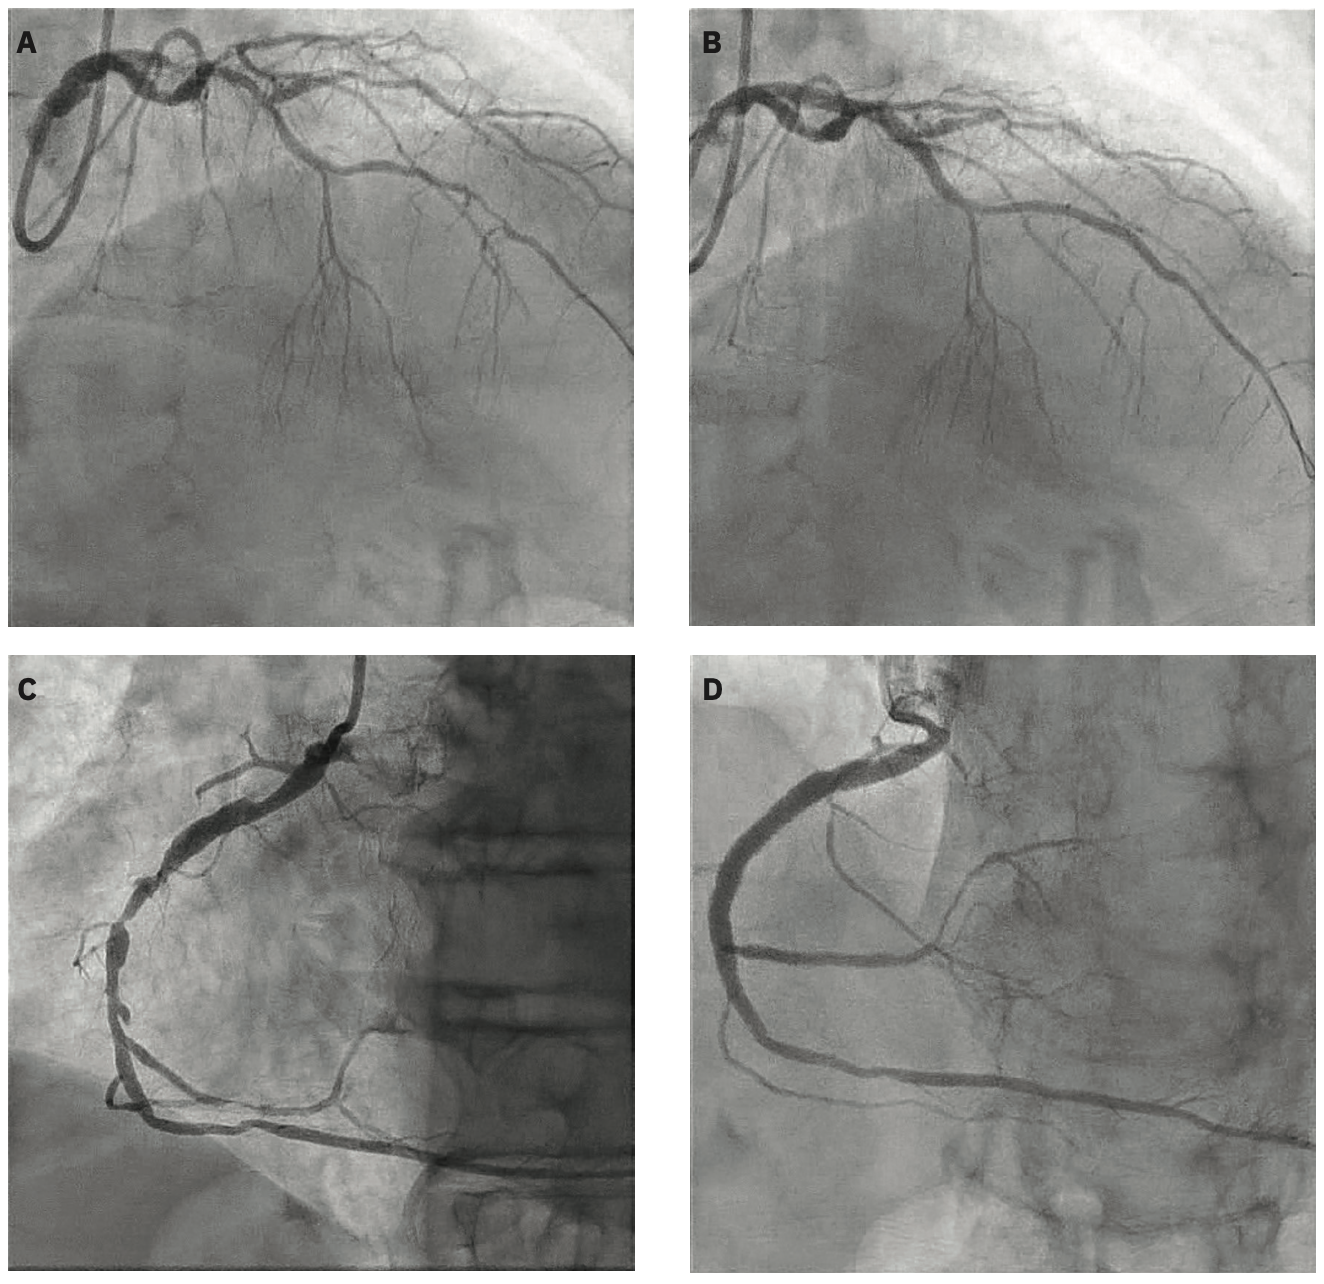

Another area where we were limited by pulses previously was using IVL in two separate vessels. There have been times when I was in a second vessel with moderate to severe calcium but had already used all of therapy in a catheter. I tried to not use IVL in these scenarios, being economically conscious, but with the extra pulses of the C2+, treating a second vessel with IVL and having enough pulses is no longer as big of a concern. While some of the previous economic concerns have been alleviated with the coding changes supporting IVL reimbursement, now with the extra 40 pulses, you often have enough pulses to treat two vessels using a single catheter.

I think of IVL first, period, just because of the lower risk profile of IVL versus other forms of calcium modification. It is a simple balloon-based therapy versus mechanical atherectomy, whether rotational or orbital, which carry a higher risk of perforation or dissection, and are technically more cumbersome to perform. When we started using IVL, many of us first thought we were going to need to use mechanical atherectomy in order to deliver the IVL balloon. However, the balloon is a great deal more deliverable than we initially thought. In our institution, we use a rota-shock or rota-tripsy paradigm in less than 10% of cases.

Also, IVL’s mechanism modifies calcium differently compared to other modalities. Rotational atherectomy modifies superficial calcium and doesn’t affect the deeper calcium, and is somewhat limited on burr size. Orbital atherectomy may have some modification of deeper calcium due to the nature of its mechanical forces. But, again, the risk profile is higher compared to IVL, so I still prefer to use IVL up front.

I use an IVL-first strategy and reserve mechanical atherectomy mostly for cases when I just can’t deliver the balloon. When I see severe calcium, the first decision is how I am going to safely modify it, independent of the pulse limitations.

The additional pulses allow us to treat longer and more lesions while maintaining this IVL-first strategy.